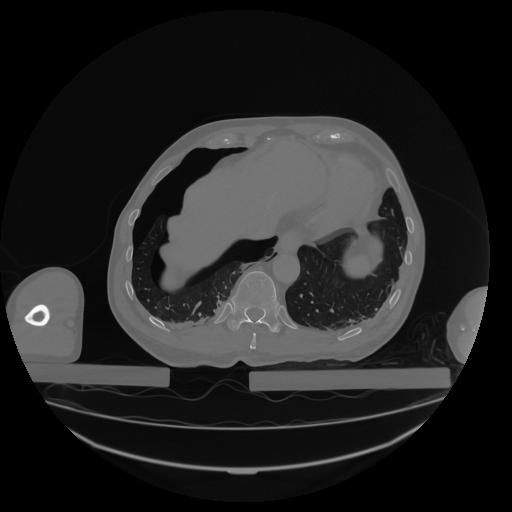

34 CUERPO,CE,Vol,1.0,CUERPO,,